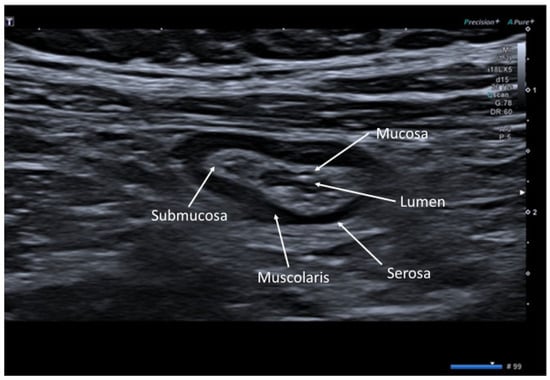

2. Ultrasonographic Anatomy of Gastrointestinal Tract